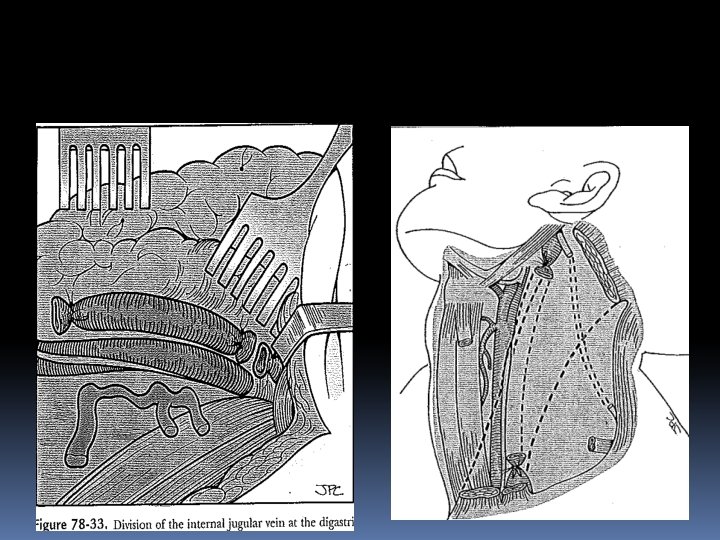

NECK DISSECTION RECONSTRUCTION MANAGEMENT OF PAIN

IN CASE OF EXTENSIVELY INVOLVED LYMPH NODES NECK DISSECTION IS INDICATED LYMPH NODES IN THE NECK ARE CLASSIFIED AS LEVELS I TO VII LEVEL IA SUBMENTAL GROUP LEVEL IB SUBMANDIBULAR GROUP LEVEL II UPPER JUGULAR GROUP LEVEL III MID-JUGULAR GROUP LEVEL IV LOWER JUGULAR GROUP LEVEL V POSTERIOR TRIANGLE GROUP LEVEL VI CENTRAL COMPARTMENT GROUP LEVEL VII SUPERIOR MEDIASTINAL GROUP

INCISIONS

RND

MRND TYPE I SPINAL ACESSORY NERVE PRESERVED

MRND TYPE II Spinal acessory nerve and IJV preserved

MRND TYPE III All 3 structures preserved

Supraomohyoid neck dissection